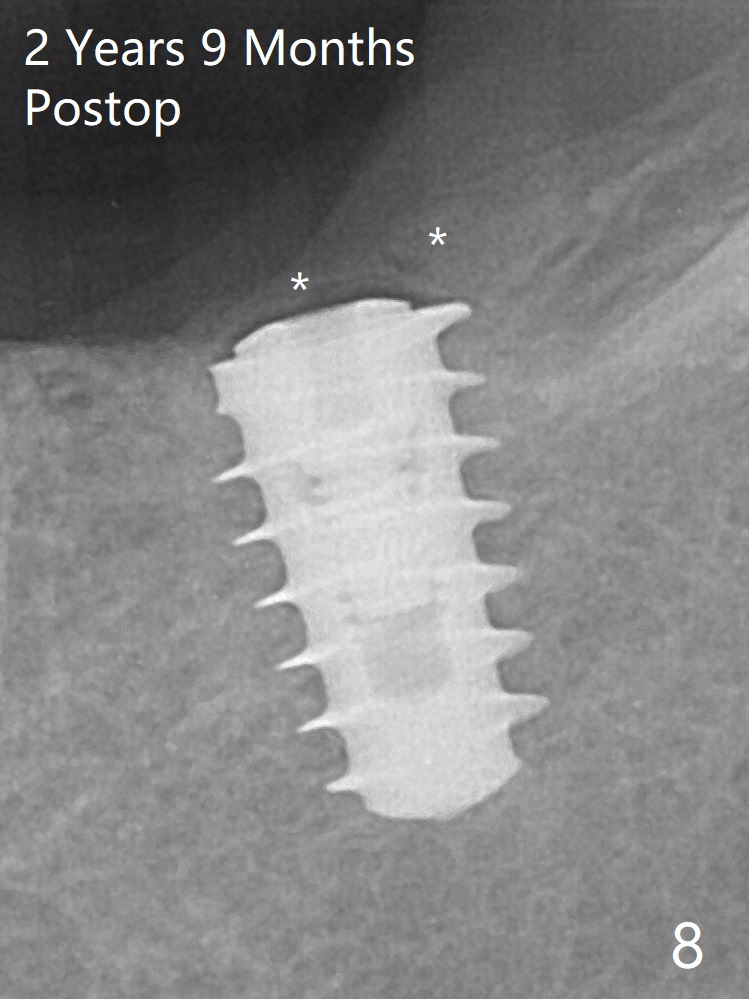

In fact the distal coronal threads of the implant are exposed due to socket morphology (Fig.2 yellow dashed line, Fig.7 red dashed line). Bone graft should be securely placed immediately distal to the implant to prevent periimplantitis. The implant plateau is covered by the bone 2 years 9 months postop (Fig.8 *).